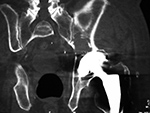

Particle disease (arrows) left hip coronal CT image |

68 year-old man with particle disease from a worn out left hip prosthesis. Bony destruction (arrows) is in the left supra-acetabular region and in the left greater trochanter with a pathologic fracture. |